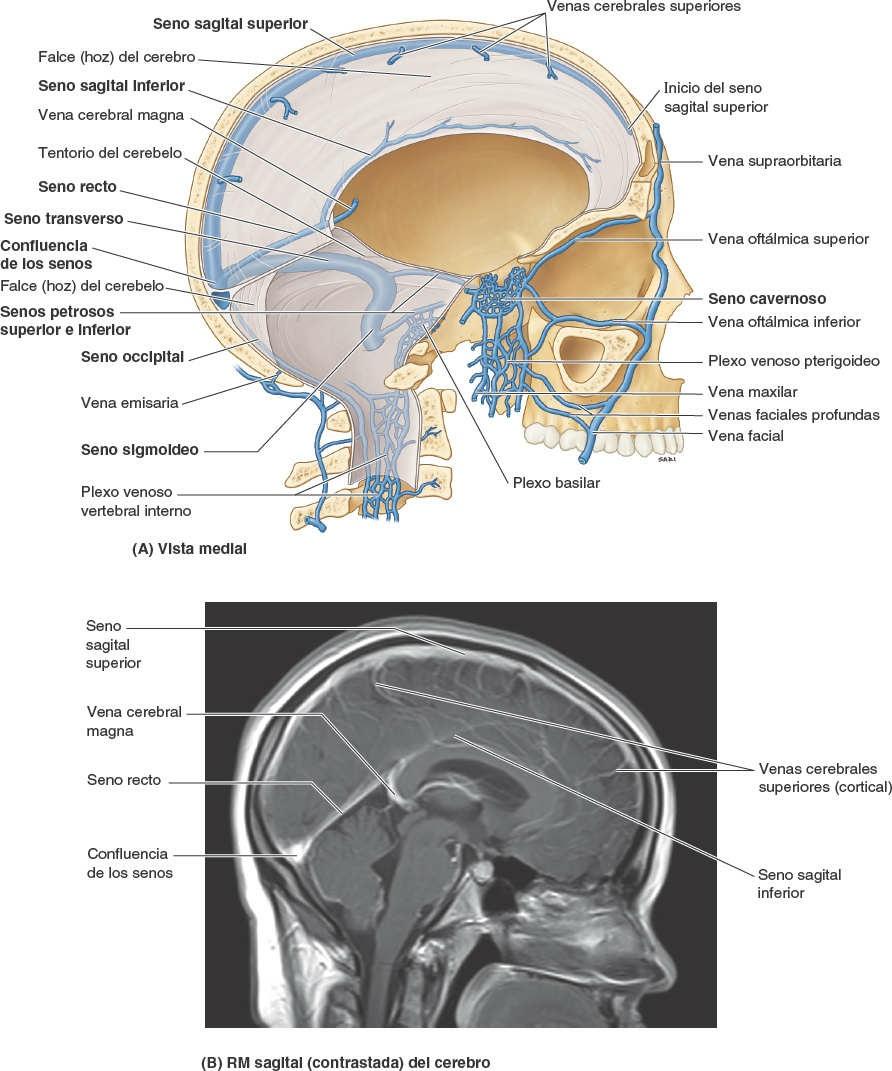

Los senos venosos de la duramadre son espacios revestidos de endotelio situados entre las capas perióstica y meníngea de la duramadre. Se forman allí donde se adhieren los septos de duramadre a lo largo del borde libre de la falce del cerebro y en relación con ciertas formaciones de la base del cráneo (figs. 8-29, 8-31 y 8-32). Las grandes venas de la superficie del encéfalo drenan en estos senos, y la mayor parte de la sangre del encéfalo drena a través de ellos en las venas yugulares internas.

El seno sagital superior se sitúa en el borde convexo de adhesión de la falce del cerebro (fig. 8-29). Se inicia en la crista galli y finaliza cerca de la protuberancia occipital interna (fig. 8-30) en la confluencia de los senos, lugar de encuentro de los senos sagital superior, recto, occipital y transversos (fig. 8-32). El seno sagital superior recibe las venas cerebrales superiores y se comunica a cada lado, a través de orificios semejantes a hendiduras, con las lagunas venosas laterales, expansiones laterales del seno sagital superior (fig. 8-29 D).

El seno sagital inferior es mucho más pequeño que el seno sagital superior (fig. 8-29). Discurre por el borde libre cóncavo inferior de la falce del cerebro y finaliza en el seno recto. El seno recto está formado por la unión del seno sagital inferior con la vena cerebral magna. Discurre inferoposteriormente a lo largo de la línea de unión de la falce del cerebro con el tentorio del cerebelo, donde se une a la confluencia de los senos.

Los senos transversos discurren lateralmente desde la confluencia de los senos y forman un surco en cada hueso occipital y los ángulos posteroinferiores de los huesos parietales (figs. 8-30 a 8-32). Los senos transversos cursan a lo largo de los bordes posterolaterales de unión del tentorio del cerebelo y luego se transforman en los senos sigmoideos cerca de la cara posterior de la porción petrosa de los huesos temporales. La sangre que llega a la confluencia de los senos drena en los senos transversos, aunque raras veces de un modo igual, pues habitualmente predomina el izquierdo (cuyo tamaño es mayor).

Los senos sigmoideos siguen un recorrido en forma de S en la fosa craneal posterior, formando profundos surcos en los huesos temporales y occipital. Cada seno sigmoideo gira anteriormente y luego continúa inferiormente como vena yugular interna después de atravesar el foramen yugular. El seno occipital se sitúa en el borde de adhesión de la falce del cerebelo y finaliza superiormente en la confluencia de los senos (fig. 8-29 B). El seno occipital comunica inferiormente con el plexo venoso vertebral interno (figs. 8-29 B y 8-33).

Los senos cavernosos, grandes plexos venosos, se sitúan a cada lado de la silla turca en la cara superior del cuerpo del esfenoides, que contiene el seno (aéreo) esfenoidal (figs. 8-29 B y 8-31). El seno cavernoso se compone de un plexo venoso de venas con paredes extremadamente delgadas, que se extiende desde la fisura orbitaria superior, anteriormente, hasta el vértice de la porción petrosa del hueso temporal posteriormente. Recibe sangre de las venas oftálmicas superior e inferior, la vena cerebral media superficial y el seno esfenoparietal. Los conductos venosos de los senos cavernosos comunican entre sí a través de los senos intercavernosos, anterior y posteriormente al tallo hipofisario (fig. 8-31 A y B), y a veces mediante venas inferior-mente a la hipófisis. Los senos cavernosos drenan posteroinferiormente a través de los senos petrosos superior e inferior, y por medio de venas emisarias en los plexos basilar y pterigoideos (fig. 8-29 A).

Los senos petrosos superiores discurren desde los extremos posteriores de las venas que componen los senos cavernosos hasta los senos transversos en el punto donde estos senos se incurvan inferiormente para formar los senos sigmoideos (fig. 8-32 B). Cada seno petroso superior está situado en el borde de adhesión anterolateral del tentorio del cerebelo, que se une al borde superior (cresta) de la porción petrosa del hueso temporal (fig. 8-30).

Los senos petrosos inferiores también comienzan en el extremo posterior de cada seno cavernoso (fig. 8-31 A y B). Cada seno petroso inferior discurre por un surco situado entre la porción petrosa del hueso temporal y la porción basilar del hueso occipital (fig. 8-30). El seno petroso inferior drena el seno cavernoso directamente en la transición del seno sigmoideo a la vena yugular interna en el foramen yugular (fig. 8-31 B). El plexo basilar conecta los senos petrosos inferiores y comunica inferior-mente con el plexo venoso vertebral interno (figs. 8-29 B y 8-33).